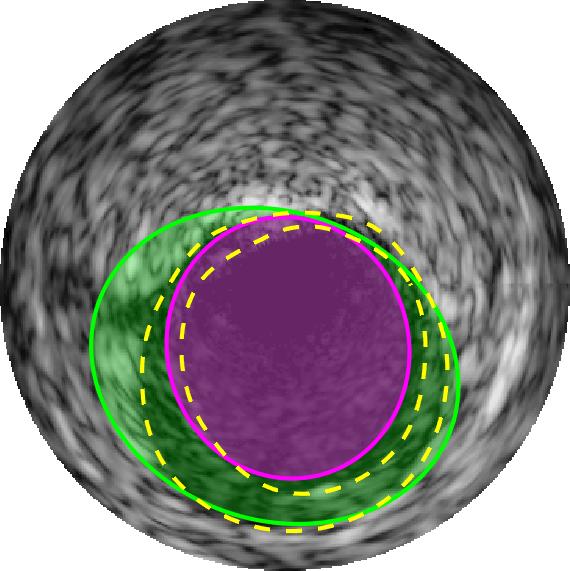

Qualitative evaluations are illustrated in Figure 4 and show the successful segmentation results of the proposed EREL selection strategy for 20 IVUS frames. The lumen areas are highlighted by the magenta colour while the media regions are green. Also, the manually annotated contours for both lumen and media are drawn as yellow dashed lines. As we can see, the chosen frames contain a variety of lumen and media morphologies.